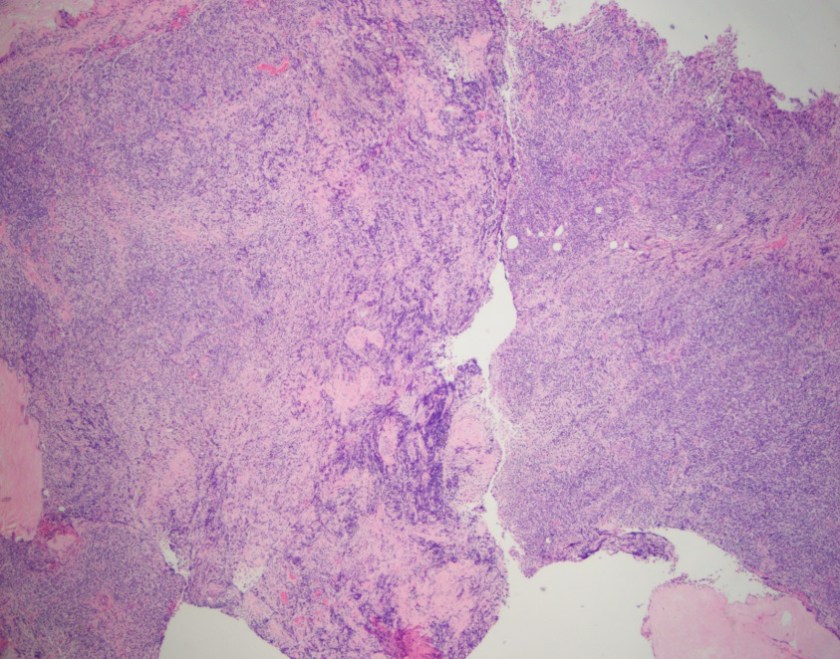

H&E, 2x

Sections show fragments of fibrous tissue and focal bone with extensive crush artifact. There is an abnormal lymphoid infiltrate with areas showing a vaguely nodular architecture. The lymphocytes are small to medium in size with irregular cleaved nuclei, inconspicuous nucleoli and small amounts of cytoplasm. Scattered centroblastic cells are seen but are <15 per high power field. Between the nodules, the cells are centrocytic appearing. Rare mitotic figures are identified.